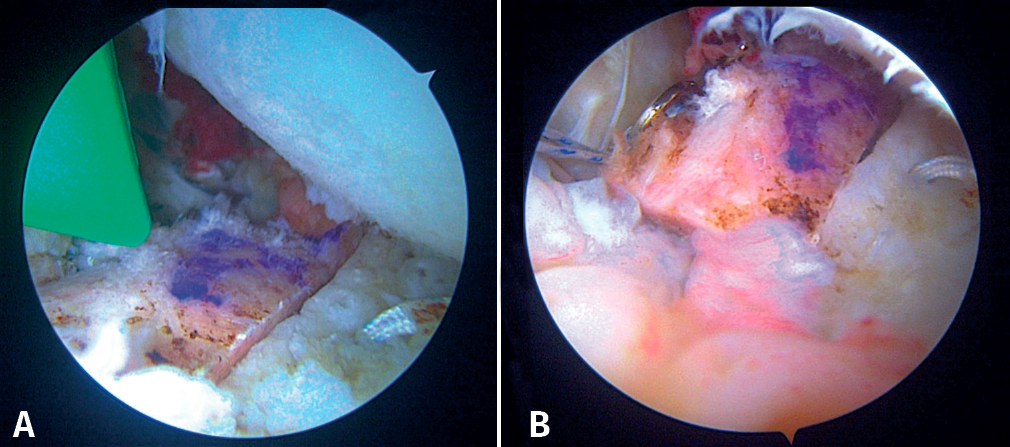

Then, the bone block (lower part first) is guided through the metal cannula or directly through the extended anterior approach, followed by loop suture pulling and tightening, one by one. The bone block is positioned with the help of the hook guide. Once the position is considered to be satisfactory (Figure 5C), the implant sutures are passed through two buttons posteriorly using the suture retriever. Both are then advanced anteriorly (with a slip knot and a knot pusher) until they rest on the posterior surface of the glenoid neck (Figures 6A and 6B). Then, the sutures threaded to the posterior buttons are knotted using a Nice-type knot and tightened, as indicated by the technique, using a specific tensor up to 50 N. After doing this with both sutures, they are tightened again to 100 N and three safety half knots are added.

Fourth step: capsulolabral plication and knotting of the remplissage